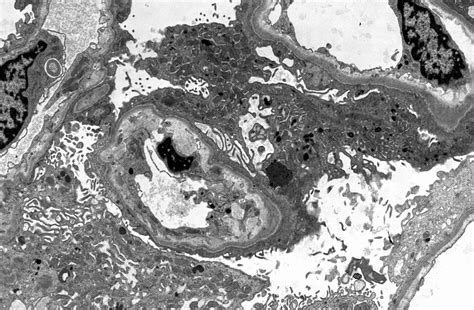

Covid Survivors More Likely to Have Kidney Problems, Study Finds - The ...